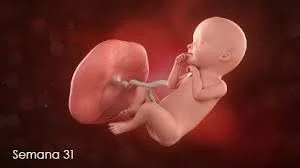

• Semana 31

Semana 31

El feto mide unos 29 cm y pesa 1.5 kg. Los sistemas digestivo y renal están completamente funcionales. Los movimientos fetales son más definidos, y el feto puede cambiar de posición. En esta etapa, empieza a practicar la deglución, preparándose para alimentarse después del nacimiento. La capa de vérnix caseosa que cubre su piel sigue creciendo.